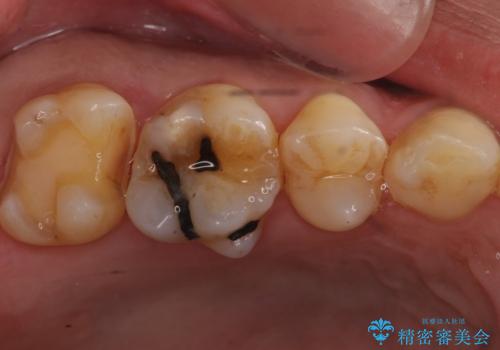

- 昔、治療された銀歯が気にな流ということを主訴で来院された患者様です。

銀歯を外し、虫歯治療を行い、セラミックインレーにて治療しました。

銀歯を除去し、虫歯をとって、セラミックインレーにて治療を行いました。